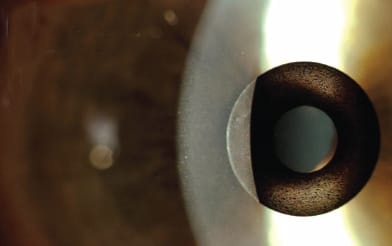

A slit-lamp image of the Flexivue corneal inlay.

■ The Presbia Flexivue Microlens (Presbia, Los Angeles). corneal inlay works by means of “smart” monovision by producing a bifocal optical system. “It actually bends light,” Dr. Gordon says. The Presbia Flexivue Microlens is implanted in the non-dominant eye of patients. “As your pupil gets smaller, patients can read because it produces a monovision effect. When the pupil dilates for distance, you’re looking around the lens, and distance vision is minimally affected.”

The central, inner zone of the Presbia Flexivue Microlens contains no refraction, and is used for distance vision (i.e., during far vision light passes through this zone of no refraction and is sharply focused on the retina). The peripheral, outer zone contains the near refractive power for near vision correction (i.e., during near vision light passes through this zone with refraction and is sharply focused on the retina). As with traditional monovision, patients require time for neural adaptation.

The Presbia Flexivue Microlens shares a virtue with other presbyopic corneal inlays in that the procedure is reversible. That can make a big difference if a patient’s visual needs evolve with age. “The beauty of this procedure is, you can select the power of the implant that you want — that’s from 1.50 D to 3.50D — and change it as the patient gets older,” Dr. Gordon says. “You can take the lens out and put in a stronger implant.” Likewise, patients dissatisfied with their vision can simply have the lens removed without negatively affecting the patient’s cornea.